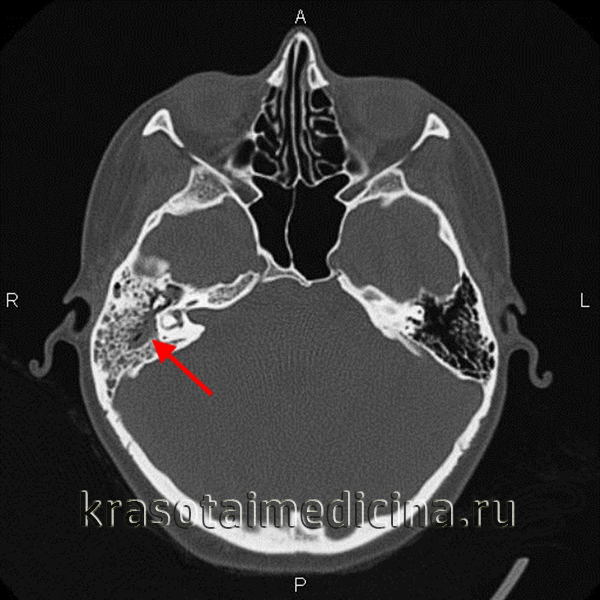

КТ височных костей. Тотальное снижение пневматизации ячеек сосцевидного отростка с обеих сторон. (фото Вишняков В.Н.)

- Рентгенография височной кости. В экссудативной стадии мастоидита обнаруживает завуалированные в результате воспаления ячейки и нечетко различимые перегородки между ними. Рентгенологическая картина пролиферативно-альтеративной стадии мастоидита характеризуется отсутствием ячеистой структуры сосцевидного отростка, вместо которой определяется одна или несколько больших полостей. Лучшая визуализация достигается при проведении КТ черепа в области височной кости.